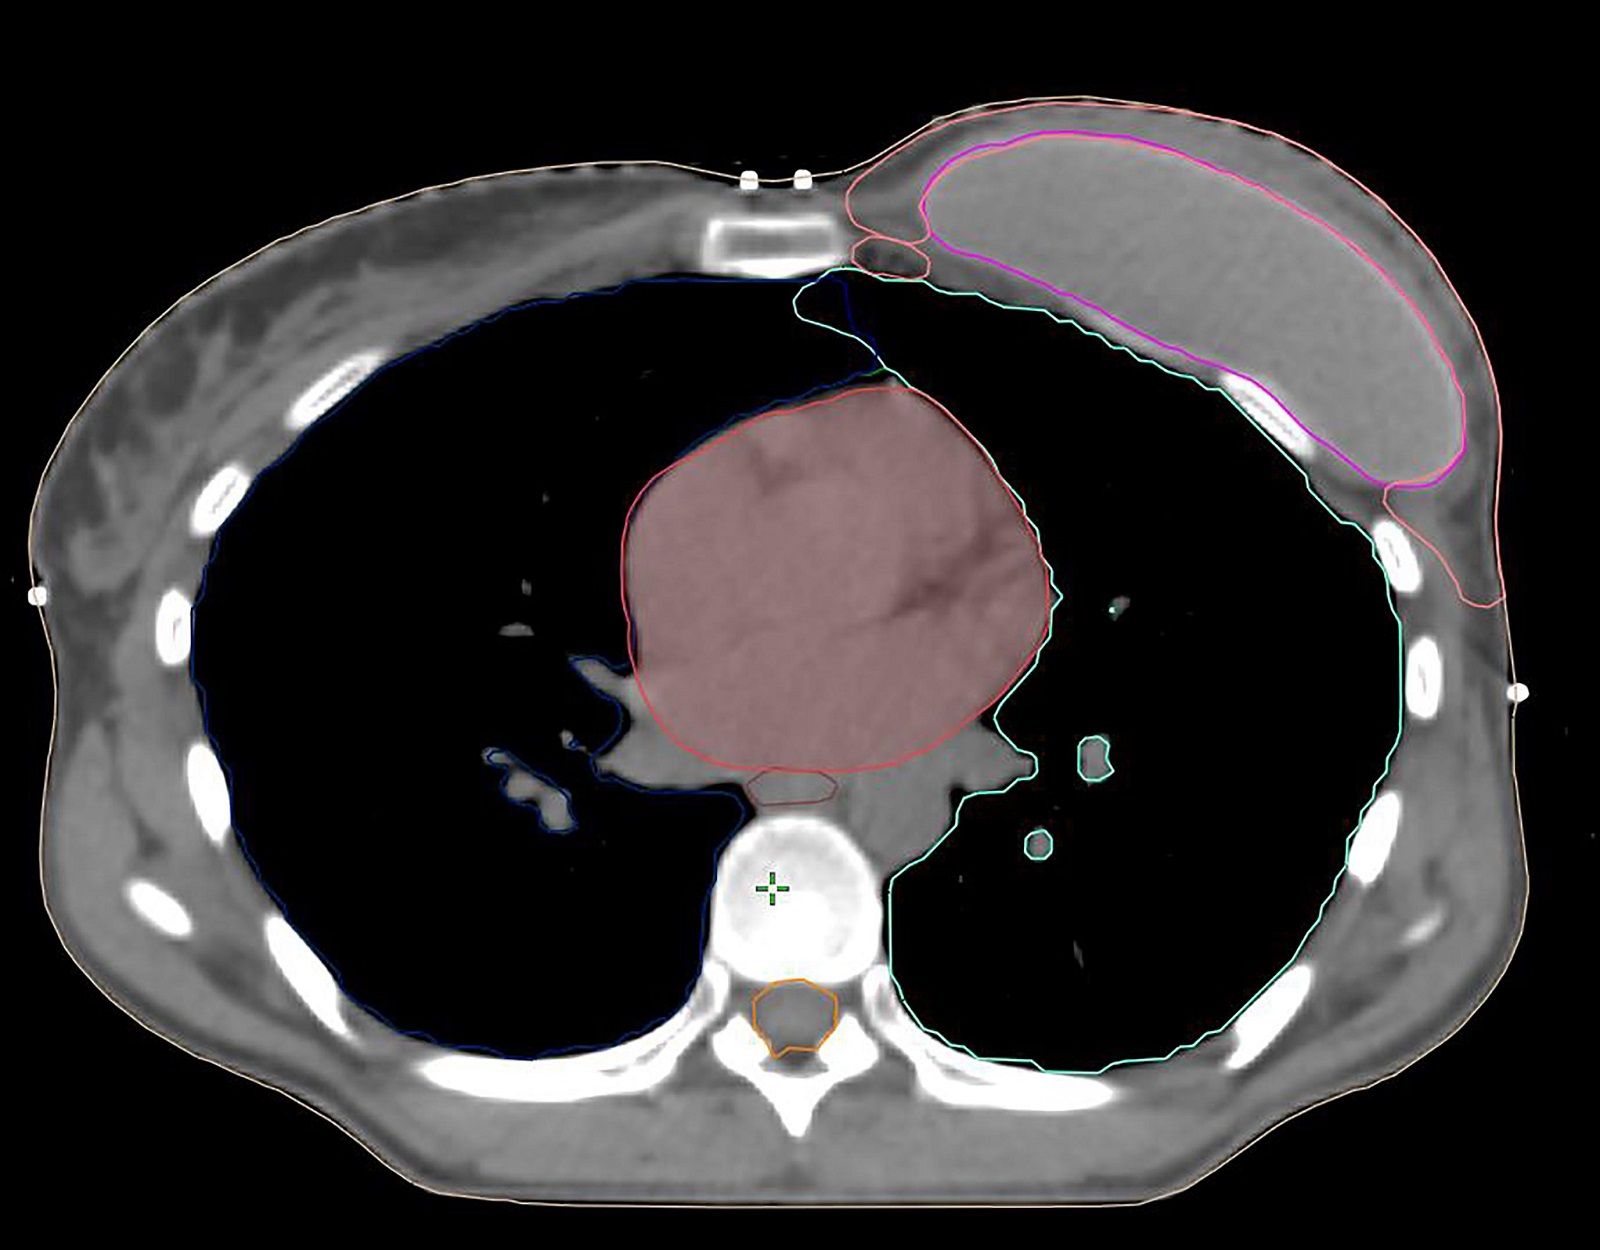

Hình 4a. CTVp_chestwall với chỉ phần trước (Màu đỏ) trong các trường hợp chỉ xạ trị mạng lưới bạch mạch dưới da. Các cơ ngực (Màu vàng) và túi độn (Màu xanh).

Nếu mạc sau tuyến vú không bị xâm lấn bởi ung thư, CTVp_chestwall cho PMRT không bao gồm mạng lưới bạch huyết sâu, do đó, chỉ bao gồm viền tổ chức mô phía trước cơ ngực lớn và túi độn, ngoại trừ ở phía trong, ngoài và dưới, nơi CTV có thể được mở rộng để bao phủ phần thành ngực không được bao phủ bởi cơ ngực lớn trước mổ. Như vậy, phần lớn túi độn có thể được loại khỏi CTVp_chestwall, trong khi các phần thành ngực xung quanh cơ ngực với các dòng chảy bạch huyết vẫn nên được bao phủ. (Hình 4a, b). Lớp cơ ngực phía trên túi độn có thể rất mỏng ở một số người bệnh, vì vậy, thể tích bia lâm sàng thường khó tránh khỏi phải bao gồm ít nhất một phần cơ ngực, nghĩa là giới hạn sau của CTV sẽ là bình diện trước của túi độn.

Với các bệnh nhân có yếu tố bất lợi và/hoặc nếu khối u nằm trong phần nhu mô tuyến sát mạc sau (Diện cắt tiệm cận, u nhuộm màu mực ở mạc sau tuyến vú) không được bao phủ bởi cơ ngực lớn (chủ yếu gặp ở các khối u phần thấp, thường nằm kết cận các xương sườn và cơ liên sườn), chỉ ngăn cách bởi mạc sau tuyến vú, chúng tôi khuyến cáo xác định thêm vùng tổ chức mô giữa thành ngực và túi độn ở phần thấp tính từ vị trí của cơ ngực lớn trước mổ (Lý tưởng nếu được đánh dấu bằng clip trong mổ), như một CTV phía sau tách biệt. (Hình 4B)

Hình 4b. CTVp_chestwall với phần trước (Đỏ) và sau (Xanh biển) trong trường hợp tổ chức bạch huyết dưới da cần được chiếu xạ cũng như phần thành ngực ban đầu không được bao phủ bởi cơ ngực lớn (Vàng). Túi độn sau cơ ngực (Xanh lá cây).